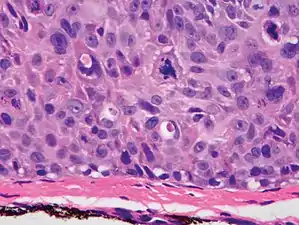

Superficially invasive cutaneous squamous-cell carcinoma. These lesions often do not show the marked pleomorphism and atypical nuclei of cSCC in situ, but manifest early keratinocyte invasion of the dermis.[12]

High magnification demonstrates the pleomorphism of the invading keratinocytes[12]